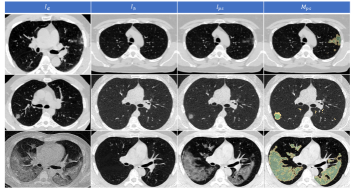

The epidemic of coronavirus disease 2019 (COVID-19) is raging around the world. Chest CT can detect small lesion areas due to its high spatial resolution and therefore is an effective imaging tool for monitoring the disease [1][2]. Automatic segmentation of lesion areas of a COVID-19 CT can facilitate medical experts in diagnosing by focusing on the Region of Interest (RoI) instead of the whole volume. Besides, statistics related to the lesion area are part of the criteria for determining the severity [3][4]. However, this task is challenging as the lesion areas are extremely varied. Three typical COVID-19 CT scans from a public dataset [5] are shown in Fig. 1. It can be seen that the lesions range from small to large, and the appearance may be of ground glass opacity, consolidation, or mixed type. Due to blurry and indistinguishable boundaries between infected and healthy areas, voxel-level labeling of lesions is not only time-consuming, but also tends to contain inconsistency between different annotators. Fig. 1 also shows the infectious annotation as ground truth (GT) along with the dataset and the manual segmentation results by two other radiologists. Since the boundary of the infected area is very fuzzy, even the segmentation results given by two experienced radiologists have obvious inconsistencies with GT.

Refer to caption

Figure 1: Typical CT scans of three COVID-19 patients from the public Dataset-A [5]. From the second row to the fourth row are the different annotations provided along with the dataset and by two other radiologists from Wuhan Union Hospital. The difference between different annotations is obvious.